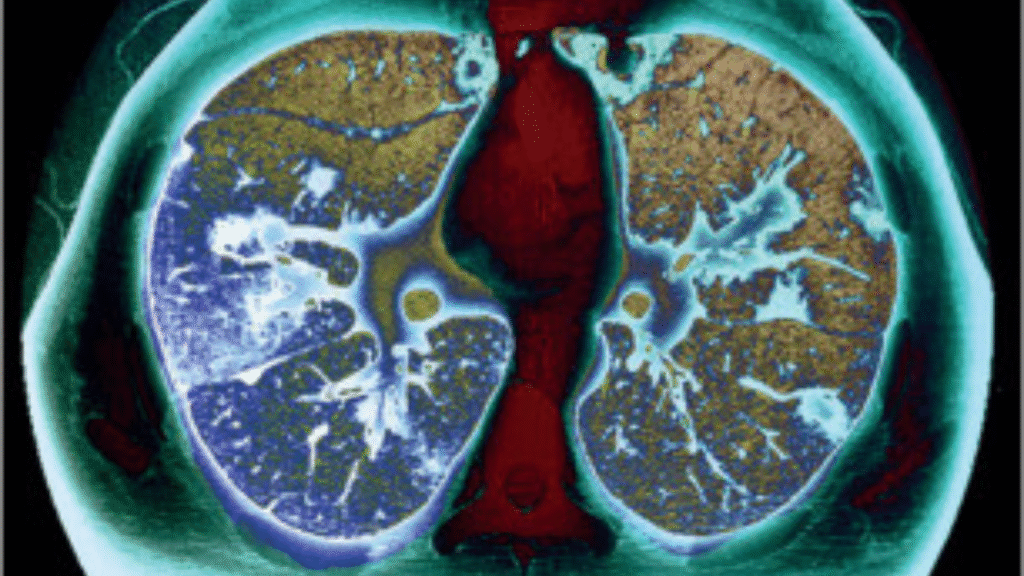

American Lung Association Calls for Expanded Insurance: Lung cancer remains the leading cause of cancer-related deaths in the United States, with tens of thousands of lives lost each year due to late-stage diagnoses. Recognizing the life-saving potential of early detection, the American Lung Association (ALA) has renewed its call for expanded insurance coverage for lung cancer screening, urging both public and private insurers to broaden access to low-dose CT scans (LDCT). This proactive move seeks to reduce barriers for high-risk individuals who could greatly benefit from early and accurate diagnosis.

The American Lung Association emphasizes that expanding insurance coverage can significantly enhance public health outcomes. Currently, lung cancer screening is recommended annually for adults aged 50 to 80 who have a significant smoking history, yet a large number of eligible individuals remain uninsured or face out-of-pocket expenses that discourage timely screenings. The ALA is pushing for comprehensive insurance reform to ensure that lung cancer screening is treated as an essential preventive service, much like mammograms or colonoscopies, with minimal to no cost for the patient.

- Early Detection: Increases survival rates significantly — early-stage lung cancer has a 5-year survival rate of 60%+.

For high-risk individuals, getting a low-dose CT scan could mean the difference between life and death. Early detection enables treatment when the disease is most manageable, significantly improving the survival rate and reducing the financial burden on families. This initiative also promotes health equity by targeting disparities and ensuring everyone, regardless of background or income, has a fighting chance against lung cancer.

The U.S. Preventive Services Task Force recommends annual lung cancer screening for adults aged 50 to 80 years who have a 20-pack-year smoking history and currently smoke or have quit within the past 15 years. Screening is conducted using low-dose computed tomography (LDCT), which detects abnormalities in the lungs at an early stage.